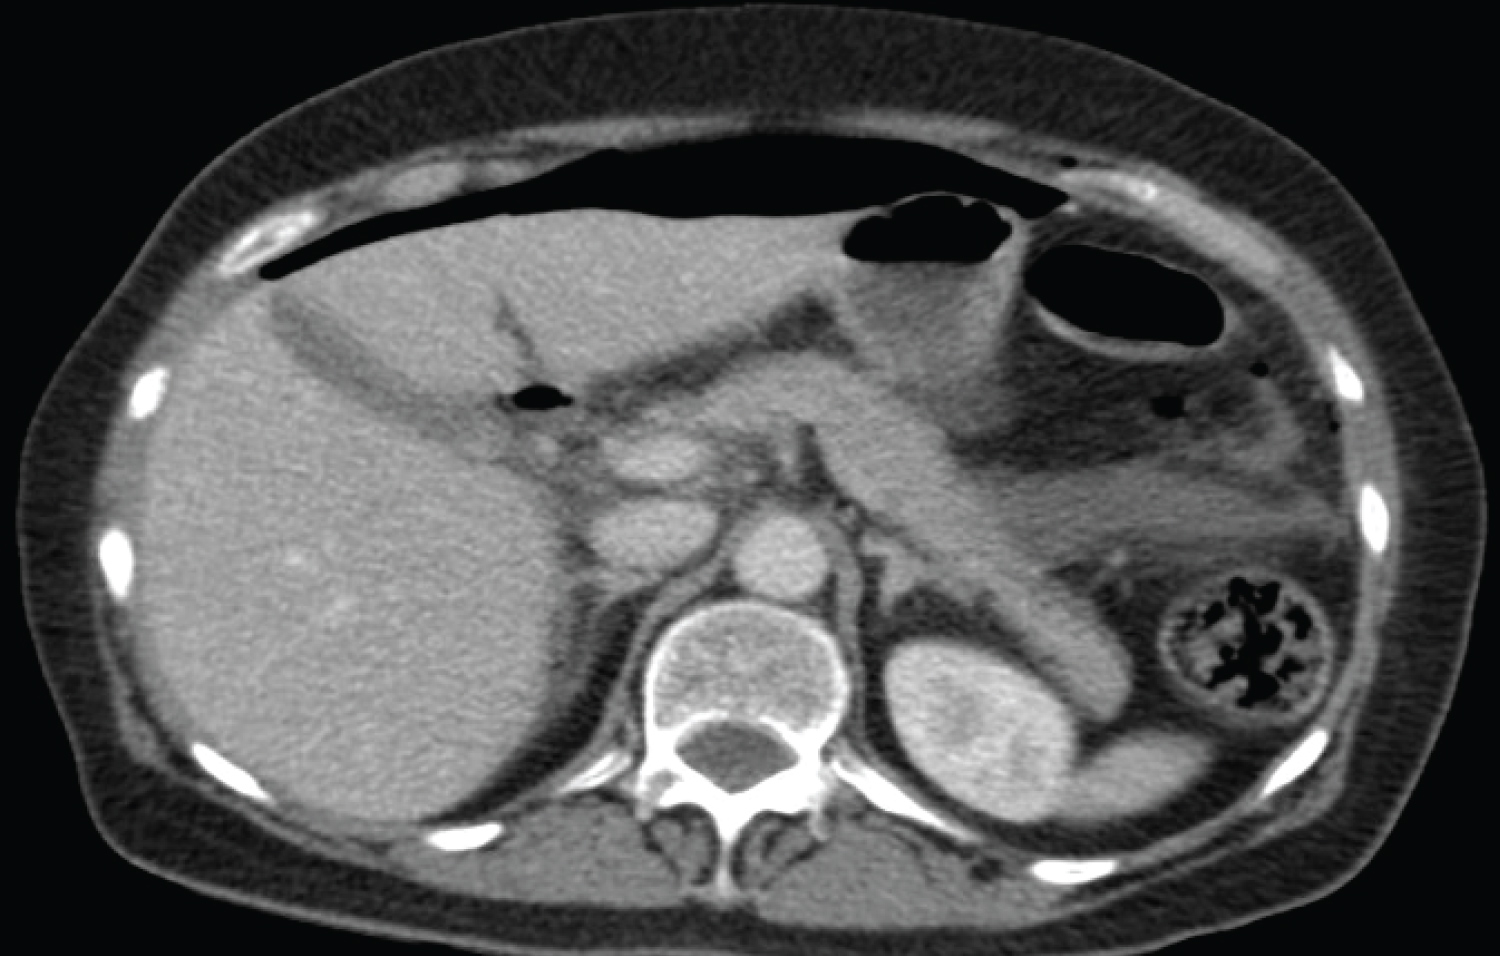

A 63-year-old woman consulted to the emergency room for abdominal pain and nausea. She had undergone an L5-S1 ALIF surgery via an anterior lumbar approach 5 days prior in another hospital. Blood tests showed no alterations and Plain X-Rays showed feces in the descending colon, without loosening of the implant. A CT scan was performed, which showed abundant intraabdominal liquid and a pneumoperitoneum (Figure 1 and Figure 2).

Figure 2: Preoperative abdominal CT scan with free liquid inside the pelvis as well as oedema and pneumatosis in the walls of the sigma. View Figure 2

The patient evolved to septic shock state, and so an emergent laparotomy was performed, showing a fecaloid peritonitis with a 1 cm-long perforation of the minor sigma, which was successfully repaired. There was no retroperitoneal extension, so the ALIF cage was not compromised. After the surgery, intravenous antibiotics were initiated.

One year later, although lumbar X-Rays show a partial loosening of the ALIF cage, she is without abdominal or lumbar pain upon gait. The surgical wound has a good macroscopical aspect and control CT scan shows no intraabdominal collections (Figure 3).

Figure 3: Control CT scan. There are no intraabdominal collections, and the ALIF cage shows a partial loosening. View Figure 3